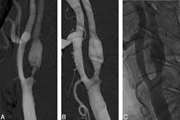

بررسی فراوانی و توصیف وضعیت بیماران به دنبال آمبولیزاسیون قبل از عمل در درمان پاراگانگلیومای کاروتید بادی؛ مطالعه ی case series 1404/01/17 - 11:49

مقایسه عوارض عروقی در بیماران مبتلا به تنگی کاروتید درمان شده با روش درمانی تعبیه استنت کاروتید بدون استفاده از protection device در مقایسه با تعبیه استنت کاروتید با استفاده از Protection device 1404/01/17 - 11:23